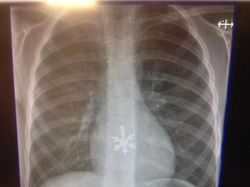

Menelan kepingan salju. (Foto: Brightside)